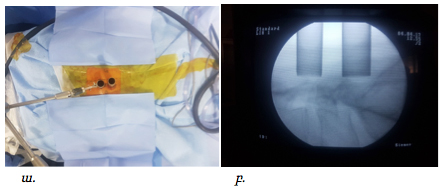

Վիրահատությունները կատարվել են ընդհանուր անզգայացման պայմաններում: Հիվանդի դիրքը փորի վրա էր: Նախքան վիրահատությունը կատարվում էր անհրաժեշտ միջողային աճառի մակարդակի որոշում՝ համաձայն կողմնային պրոեկցիայում կատարված ռենտգեն հետազոտության: Մաշկի գծային կտրվածքըկատարվում էր միջին գծից լատերալ մոտ 1.5-2սմ այնպես, որ համապատասխաներ ելունային հոդի մեդիալ սահմանին, ինչը որոշվում է հսկիչ ռենտգեն հետազոտմամբ առաջահետին պրոեկցիայում:

Վիրահատական մուտքի պլանավորումը ցույց է տրված նկար 1 և 2-ում:

Նկ. 1 Ներվիրահատական լուսանկար: Պատկերված է L4-L5 միջողային մակարդակի վիրահատման համար գծային կտրվածքը՝ մոտ 1.5սմ երկարությամբ (ցույց է տրված սլաքով)

Նկ. 2 Ներվիրահատական ռենտգեն նկար՝ վիրահատական մուտքի պլանավորում

ա. Կողմնային պրոեկցիայում ասեղը տեղադրված է L4-L5 մակարդակին:

բ. Առաջահետին պրոեկցիա՝ ասեղի ծայրը գտնվում է ելունային հոդի միջային եզրին

Վերը նշված գործողություններից հետո կատարվում էր փափուկ հյուսվածքներիգծային կտրվածք մոտ 1.5սմ երկարությամբ: Հաջորդաբար տեղադրելով փափուկ հյուսվածքներում փեղեքող գլանաձև լայնիչները (4-15մմ) ստեղծվում էրվիրաբուժական մուտք դեպի համապատասխան մակարդակ: Տեղադրվում էր աշխատանքային խողովակը, որի անշարժ դիրքը ապահովում էր երեք հարթություններում պտտվող և համապատասխան դիրքում ֆիքսվող բռնիչը:Նրամի ծայրը ամրացվում է վիրահատական սեղանին, իսկ մյուսը՝ աշխատանքային խողովակին: Նկար 3-ում պատկերված է աշխատանքային խողովակը համապատասխան դիրքում, նրա անշարժացումը ապահովող բռնիչը և տեղադրված 150 դիտարկման անկյուն ունեցող աշխատանքային էնդոսկոպը:

Նկ. 3 Ներվիրահատական նկար. Պատկերված է աշխատանքային խողովակը

ա. Աշխատանքային խողովակը ըստ ռենտգեն հետազոտման գտնվում է համապատասխան մակարդակին (L4-L5)

բ. Պատկերված է աշխատանքային խողովակը ֆիքսված բռնիչով և նրա մեջ տեղադրված էնդոսկոպը